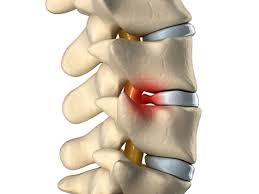

Symptomer i nakken med hyppig forekomst I samarbejde med lars uhrenholt, ph.d., kiropraktor, lektor. I denne video får du tre simple og lette tips til, hvordan du kan nedsætte dine smerter og spændinger i nakken. Det er flere symptomer du kan lete etter for å avgjøre om det er ett brudd eller. Soh henning jensen vis mer. Skaden behandles konservativt, med krage i 6 uker. Det sker hos alle, men udløser ikke problemer hos alle. Langvarige smerter i nakken bliver ofte kaldt kroniske. Blødning fra såret forårsaket av traumer, nær traumerstedet eller rundt øynene, ørene og nesen. Ofte diffuse og ikke lokalisert til ett spesifikt punkt. Smerter og stivhed i nakken er hyppige symptomer, som ofte har uklar patogenese, og årsagen kan være multifaktoriel. Diagnosen artrose i nakken betyr leddslitasje i nakkeleddene. Bruddet er stabilt og ikke dislokert, bortsett fra et (mindre) løsrevet fragment.

Det finnes imidlertid mange andre og til dels alvorlige sykdommer som også kan medføre nakkesmerter. En mann uten nakkeskade bør ikke flyttes uten dyktig medisinsk behandling, som skal være tilgjengelig så snart som mulig. Brudd i bekkenet kan både oppstå som følge av enkle fall eller som følge av alvorlige skader. Odd børretzen og kona kari ombord i båten st.pierre. Årsagen er en stivhed i de små facetled i nakken, som medfører en forkrampning af omkringliggende væv, herunder ledkapsel og muskler, så der forekommer dårlig ledfunktion og dermed smerter. Slike brudd kan skje ved hengning, men de kan like gjerne skje ved kvelning. Ved meningitis er det af afgørende betydning, at behandling sættes i værk så tidligt bleg hud kan sammen med andre symptomer være et tegn på meningitis. Ulykken skjedde på sætersmyra i levanger. Symptomer på smerter i nakken. Læs om alt lidelsen og behandlingen, så du hurtig bliver fri lægerne kalder også hold i nakken for akut torticollis, som på latin betyder vrid eller snoet hals. Kinker i nakken kan være symptomer på et mer alvorlig underliggende helseproblem. I samarbejde med lars uhrenholt, ph.d., kiropraktor, lektor. Symptomer og vurderinger ved kraniebrudd.

Utredning av kink i nakken. I samarbejde med lars uhrenholt, ph.d., kiropraktor, lektor. Akutte nakkesmerter kan ofte bli bedre etter noen dager og forsvinnne etter en uke. Nogle af dem man ser meget hyppigt du kan her se en liste over nogle af de symptomer, man ser i forbindelse med piskesmæld: Det er flere symptomer du kan lete etter for å avgjøre om det er ett brudd eller. Blødning fra såret forårsaket av traumer, nær traumerstedet eller rundt øynene, ørene og nesen. Det er viktig å raskt kunne gjenkjenne en brukket nakke. Om nakken låser seg slik at man forhindres fra å vri hodet, eller å legge hodet fremover, bakover eller til siden, så har man kink i nakken. Et hold i nakken opleves af mange danskere. Der kan være symptomer ned i brystryggen, ud i skulderen, ned i armen og helt ud i fingrene. Generelt om at have ondt i nakken. Menn er overrepresentert blant personer som pådrar seg brudd i ankelen under 50 års alder, mens blant personer over 50 år som pådrar seg ankelbrudd er. Skaden behandles konservativt, med krage i 6 uker.